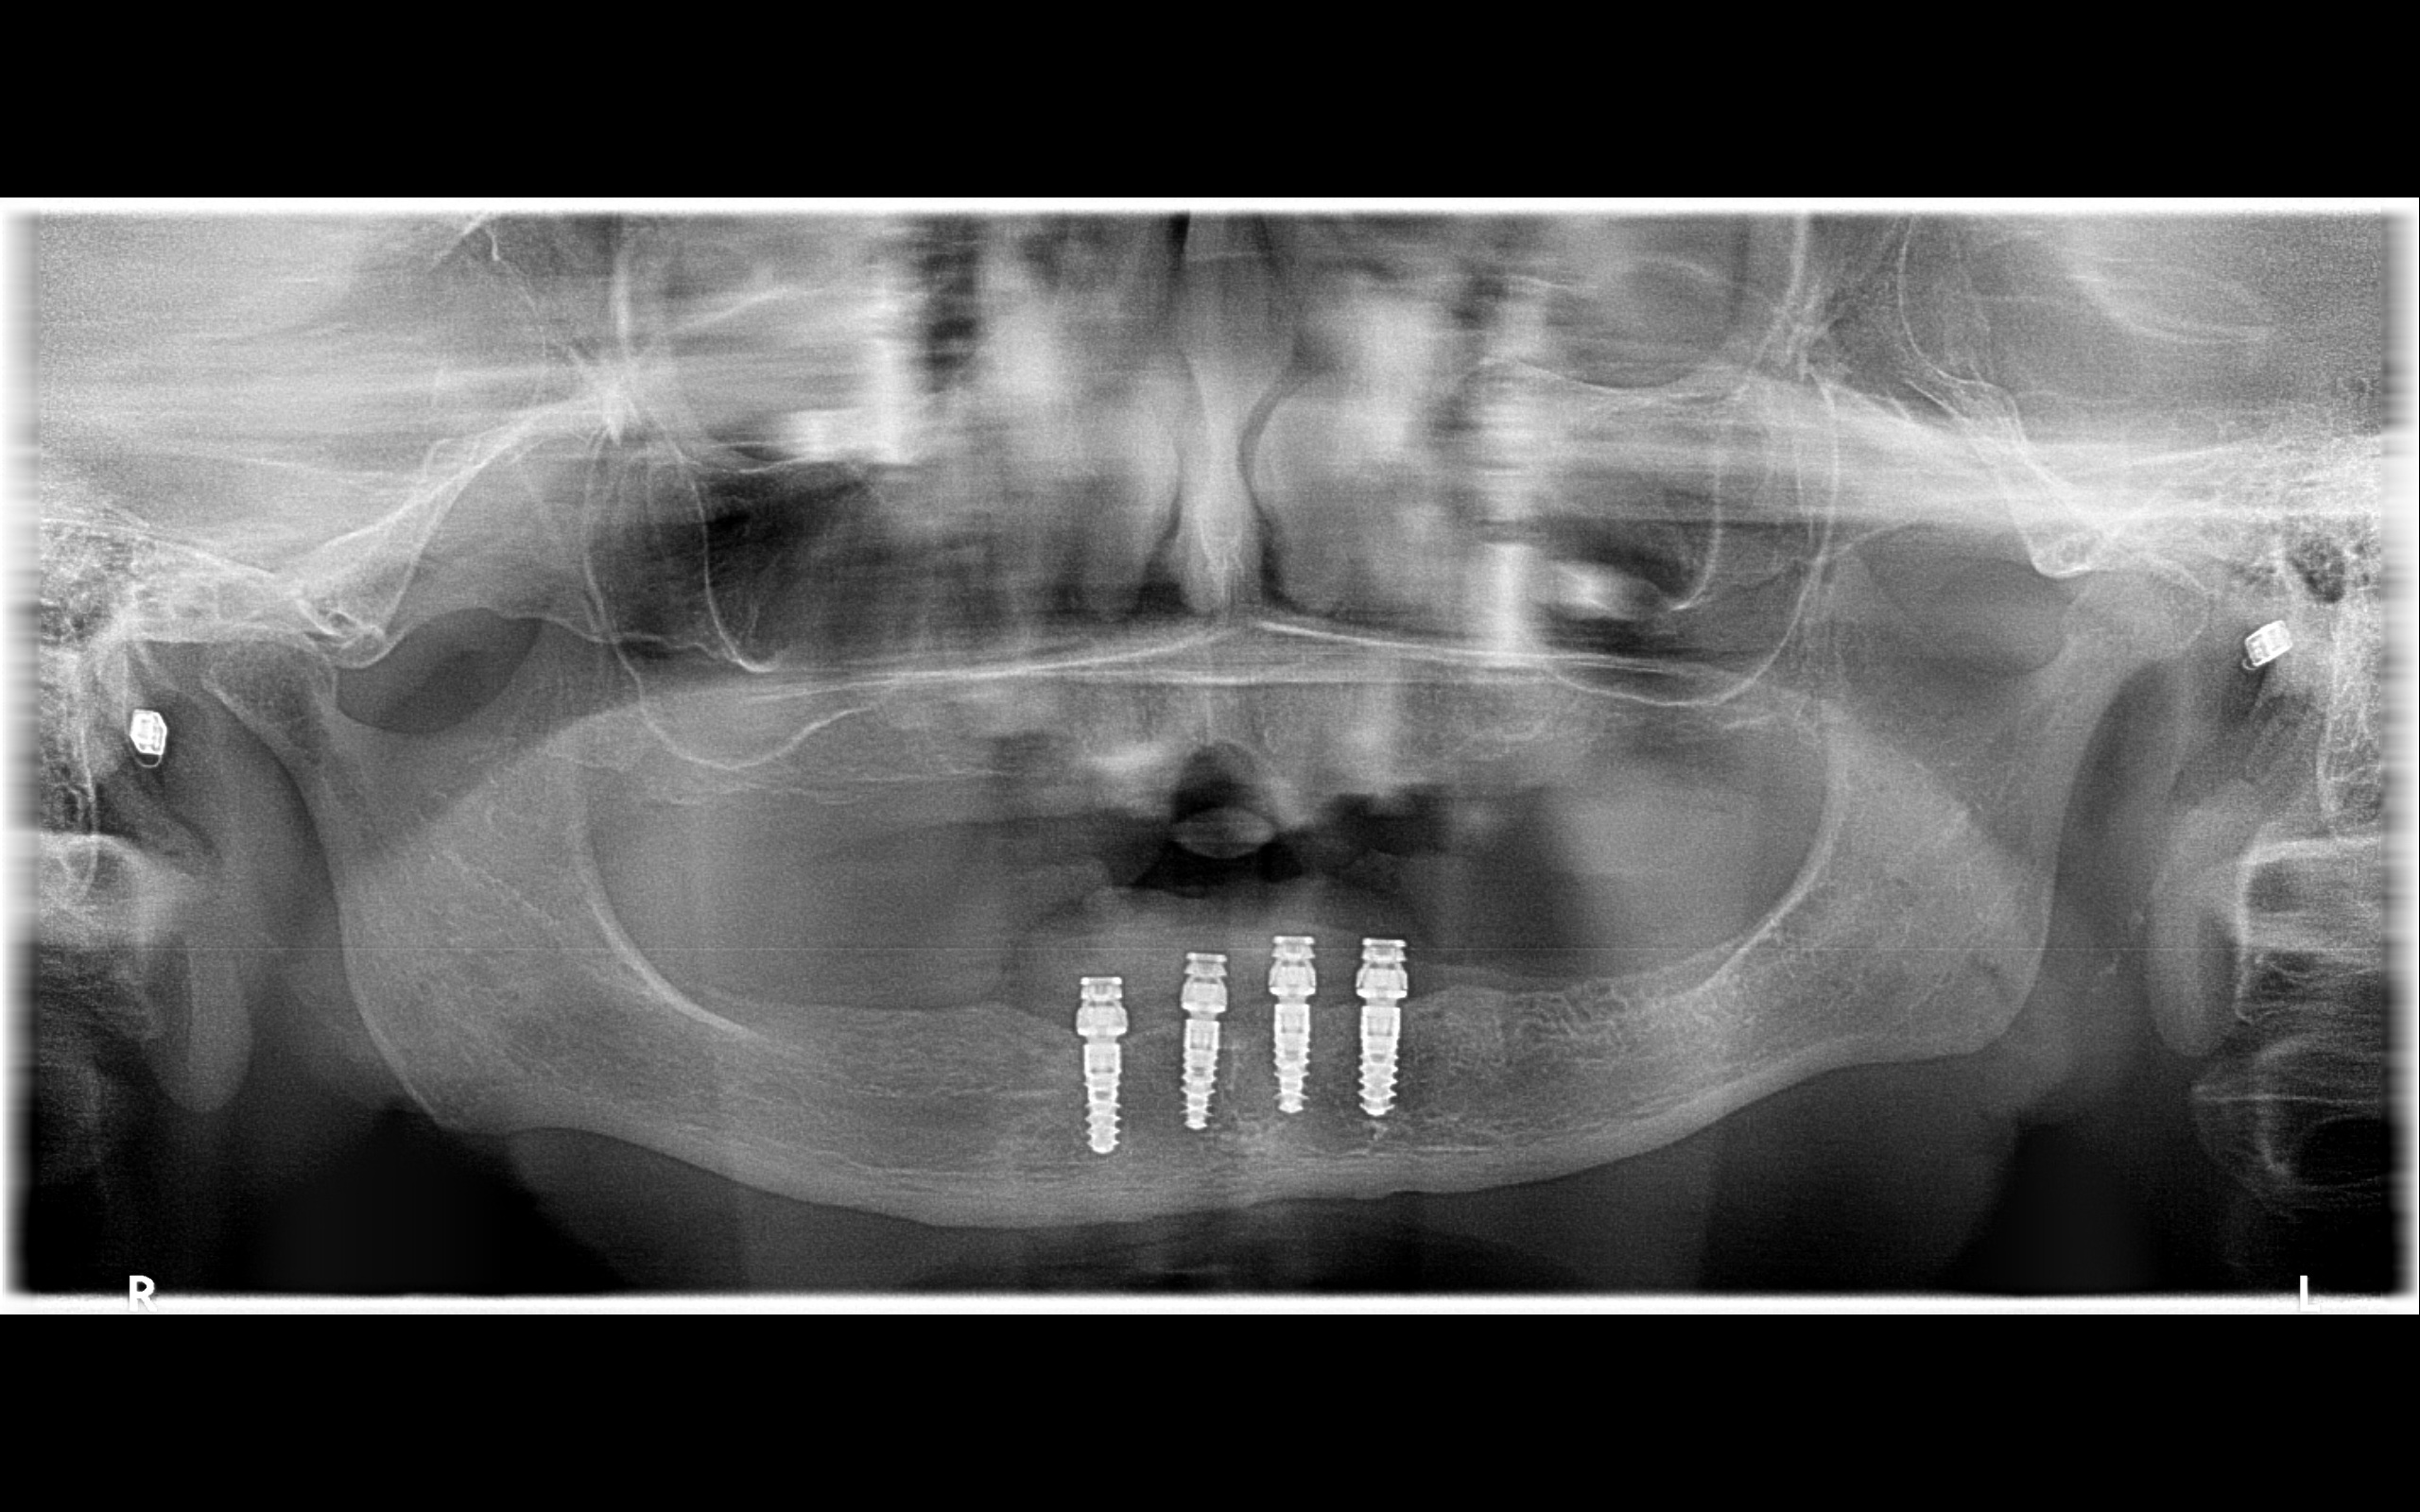

歯科でいう診断とは、ただ悪い場所を見つけることではありません。治療後にどれだけ長く安定しやすいかを予測する作業です。そのため、CTという三次元の画像検査で骨の厚みや病変の広がりを確認し、噛み合わせの接触や歯ぎしりの傾向まで含めて判断します。CTとは、骨や神経の位置を立体的に確認できる検査です。米国の補綴学では、補綴物を入れる前に「その歯列全体が長く機能する設計か」を先に考える文化が強く、1本単位の処置だけで話を終えません。補綴学とは、失われた歯や噛む機能を回復する歯科の分野です。

たとえば奥歯を1本失うと、前歯で噛む割合が増え、被せ物や残っている歯に負担が移ります。奥歯は咬合支持といって、噛む力を後方で支える役割を持ちます。これが減ると、見た目の問題より先に、食事のしづらさや顎の疲れとして表れることがあります。補綴の視点では、インプラントは「空いた場所を埋める治療」ではなく、「どこに力を戻すかを設計する治療」です。だから、名古屋で「名古屋 インプラント」を検討する方にこそ、CT画像、模型、咬合記録を使った診断の質を見ていただきたいと考えています。